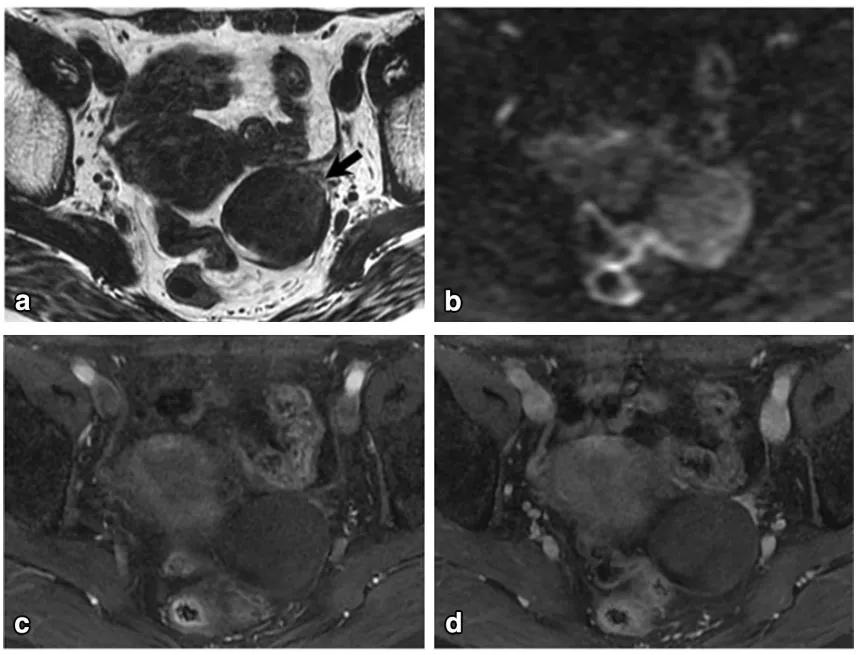

女,65 岁,左侧卵巢纤维瘤。图 a 箭头显示肿物 T2WI 呈低信号,DWI 未见明显扩散受限(b),增强扫描缓慢强化(c 增强早期,d 增强晚期)

女,32 岁,富于细胞性纤维瘤。右卵巢实性为主肿物,T2WI 稍高信号(图 a),DWI 高信号(图 b),增强扫描渐进行强化(c 增强早期,d 增强晚期)